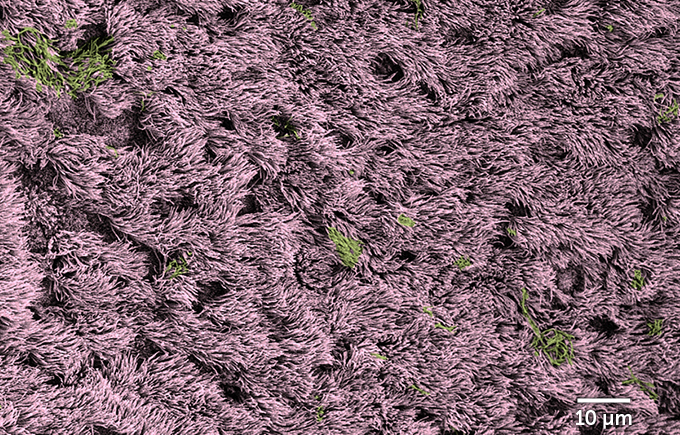

Uninfected cells grew in lawns resembling lush grasslands, where the tufts of waving fronds are actually hairlike protrusions called cilia, which grow from the tops of airway-lining cells, the team confirmed. Cilia’s motions help move mucus, and anything stuck in the mucus, out of the lungs.

Cells infected with the coronavirus looked much different. The lush lawn was now slathered in mucus, and bald spots appeared as infected cells died. The doomed cells get squeezed out of the lawn of cilia and inflate like a balloon. The inflation happens partly because chambers called vacuoles inside the infected cells get clogged with viruses. “It’s just filled with viruses, and then it gets kicked out of the club and it blows up and releases all these viruses,” Dickey says.